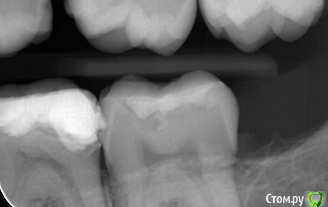

Руслан81 Опубликовано 5 октября, 2017 Автор Поделиться Опубликовано 5 октября, 2017 (изменено) А вот тут сказал на нижней 6-ке нужно переделать пломбу-межзубной кариес Изменено 5 октября, 2017 пользователем Руслан81 Ссылка на комментарий

DmitrySH Опубликовано 5 октября, 2017 Поделиться Опубликовано 5 октября, 2017 А вот тут сказал на нижней 6-ке нужно переделать пломбу-межзубной кариесПломба обширная, в идеале поменять на керамическую вкладку. Будет долговечнее. Но сперва вылечить соседний 37 зуб 1 Ссылка на комментарий

DmitrySH Опубликовано 5 октября, 2017 Поделиться Опубликовано 5 октября, 2017 на снимке в посте №6 видна кариозная полость на передней поверхности зуба 37, на последнем снимке хуже видно Ссылка на комментарий